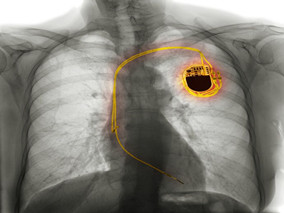

心脏静脉狭窄患者手术一波三折 电极导线断裂怎么办?

1小时条评论老年女性患者心慌、气短、不能平卧,入院后诊断为扩张型心肌病。经药物强化治疗后行CRT植入术,因患者心侧静脉和心后侧静脉狭窄,在使用球囊的情况下仍不能送入左室电极导线,手术失败。12日后,行心外膜左室电极导线植入术成功。3年后,患者因左室心外膜电极导线断...